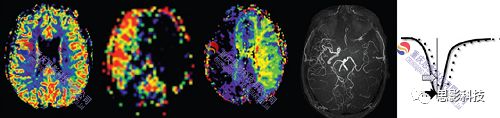

1.     數(shù)據(jù)預(yù)處理:

具體包括:數(shù)據(jù)轉(zhuǎn)換、圖像復(fù)位、頭動(dòng)校正、配準(zhǔn)、平滑、去除顱外體素、計(jì)算CBF等。

2.CBF統(tǒng)計(jì)計(jì)算: